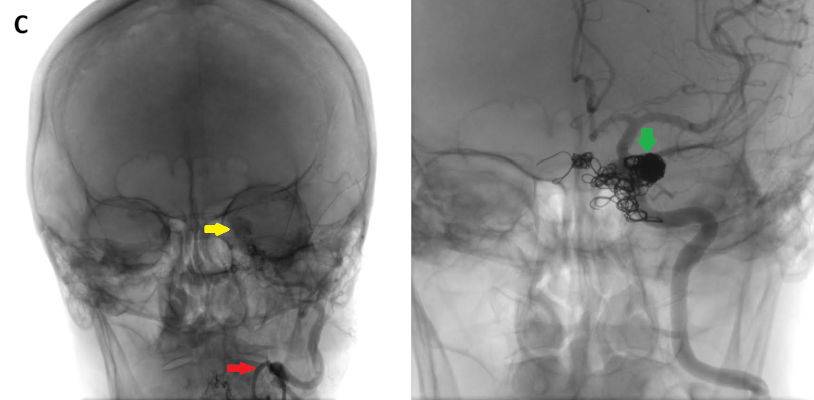

- C) DSA incelemelerinde sol eksternal karotid arter (ok) kateterizasyonunda kontrast maddenin kavernöz sinüse (ok) geçtiği izleniyor. Tedavi sonrası görüntüde kavernöz sinüs ile karotis arteriyel sistem arasında bulunan fistül traktına coil embolizasyon (ok) işlemi uygulandığı görülüyor.

- DSA: Fistülün akış hızını karakterize ederek direkt ve indirekt fistülleri net olarak ayırabilir. ICA defektinin tam anatomik yerini ve ICA veya ECA dural besleyicilerini gösterir. Ayrıca DSA ile endovasküler tedaviler yapılabilmektedir.

- Olgumuzun DSA incelemelerinde sol ICA ve ECA’dan kavernöz sinüse fistülöz bağlantı olduğu izlenmiş ve coil embolizasyon işlemi uygulanarak tedavi edilmiştir.